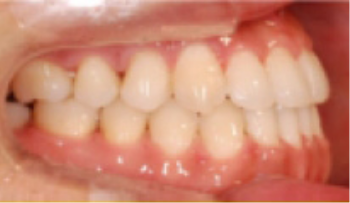

교정치료 Before&After

• 상악 전돌(돌출) 위턱이 앞으로 나옴.

Before

After